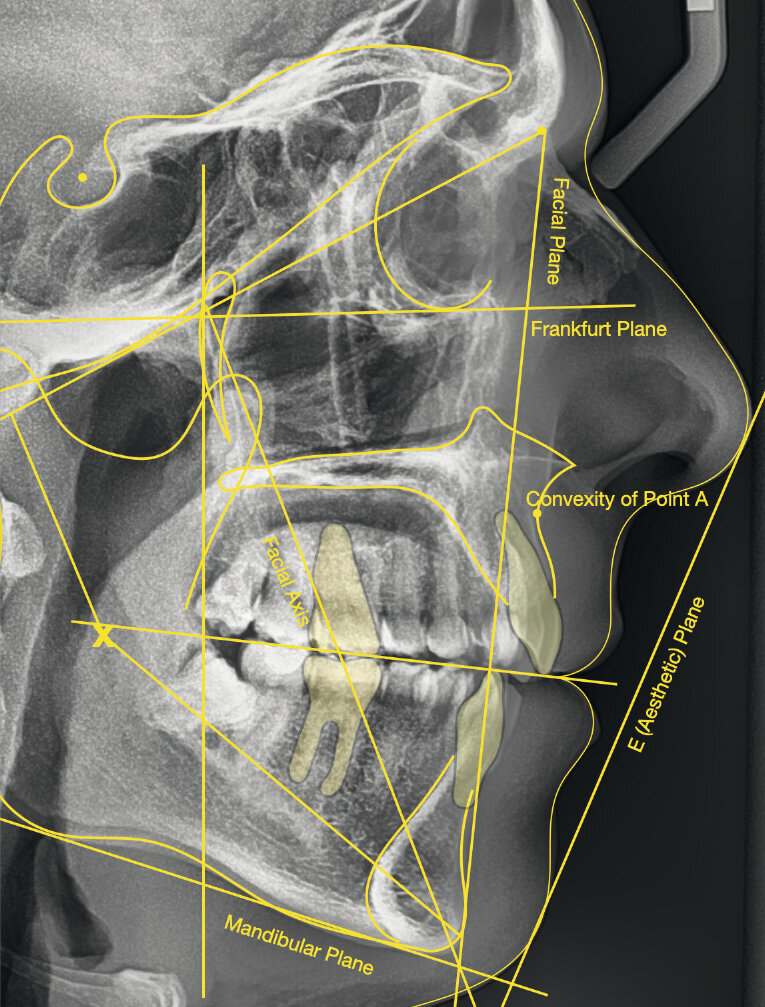

Dal punto di vista parodontale il paziente ha mostrato una buona attitudine all’igiene orale, ma l’affollamento degli incisivi mandibolari ha reso difficile la pulizia in quell’area, causando un accumulo di placca e un’infiammazione gengivale localizzata. La radiografia panoramica ha rivelato la presenza dei terzi molari mandibolari e ha confermato l’assenza dell’incisivo centrale mandibolare destro (Fig. 10). L’analisi cefalometrica ha evidenziato una malocclusione scheletrica di Classe II (convessità del Punto A: 4,9 mm), una posizione leggermente retrusa del mento (profondità facciale: 78,1°) e una tendenza scheletrica al morso aperto (altezza facciale inferiore: 53,19°; asse facciale: 80,58°; Fig. 9). Gli incisivi mandibolari erano inclinati lingualmente (Li-APog: 9,3°) e retrusi (Li-APog: 1,55 mm), con un angolo interincisivo aumentato di 142,9°.